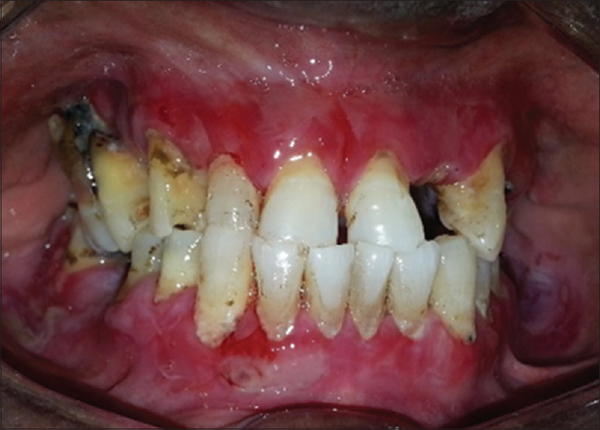

Атрофический вид заболевания слизистой ткани

Возникает из-за плохой гигиены полости рта, в результате чего образуется кариес, налёт, камни, что пагубно действует на состояние дёсен.

Фото 5. Атрофический гингивит десен и полости рта – запущенная форма болезни с паталогическим перерождением эпителиальной ткани.

Отличительная черта такого гингивита – его неизлечимость. Поэтому важно не допустить переход любого воспаления в атрофическую форму.

Все меры лечения атрофического типа гингивита направлены на остановку разрушительного процесса.